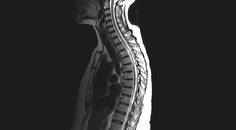

Case Report: Longitudinally Extensive Transverse Myelitis

Ylec Mariana Cardenas, MD; Lakshmi Leishangthem, MDYlec Mariana Cardenas, MD; Lakshmi Leishangthem, MD - Imaging & Testing